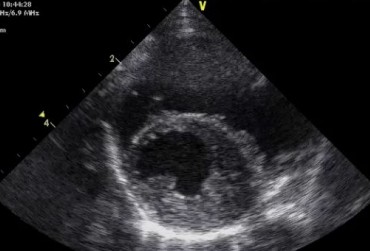

Dysplazja zastawki trójdzielnej i zespół Wolffa–Parkinsona–White’a u kota – opis przypadku

Zwężenie zastawki trójdzielnej jest jedną z form dysplazji pojawiającą się w różnym stopniu nasilenia (najczęściej łącznie z niedomykalnością zastawki) zarówno u psów, jak i u kotów. Cechami charakterystycznymi definiującymi zwężenie zastawki trójdzielnej są: obecność rozkurczowego wybrzuszenia (doming) płatków zastawki, zmniejszona ruchomość płatków, zmniejszona średnica ujścia zastawki. Mimo że zmiany morfologiczne aparatu trójdzielnego są typowe w przebiegu TVD i są znakiem rozpoznawczym tej choroby, nie są one zawsze bardzo silnie wyrażone i nie zawsze można mieć bezsprzeczną pewność diagnostyczną, bazując na badaniu echokardiograficznym [10]. Przypadki takie zdarzają się przede wszystkim u pacjentów, u których nie postawiono diagnozy we wczesnym etapie życia, a którzy pojawiają się na badaniu dopiero w starszym wieku z zaawansowanymi zmianami i niejednokrotnie z klinicznymi objawami prawostronnej niewydolności mięśnia sercowego i towarzyszącymi zaburzeniami w rytmie. W takich przypadkach obraz choroby może przypominać arytmogenną kardiomiopatię prawokomorową (arrhythmogenic right ventricular cardiomyopathy – ARVC) [1, 8]. Preekscytacja jest często obserwowana u ludzi z anomalią Ebsteina. U zwierzat, podobnie jak u ludzi, obecność dodatkowej drogi przewodzenia może nigdy nie prowadzić do rozwoju tachykardii nadkomorowej lub arytmia ta pojawiać się może dopiero w późniejszym okresie życia. Opisany przypadek jest przykładem pacjenta z dysplazją zastawki trójdzielnej i prawostronną niewydolnością serca będącą najprawdopodobniej konsekwencją tachykardii nadkomorowej.